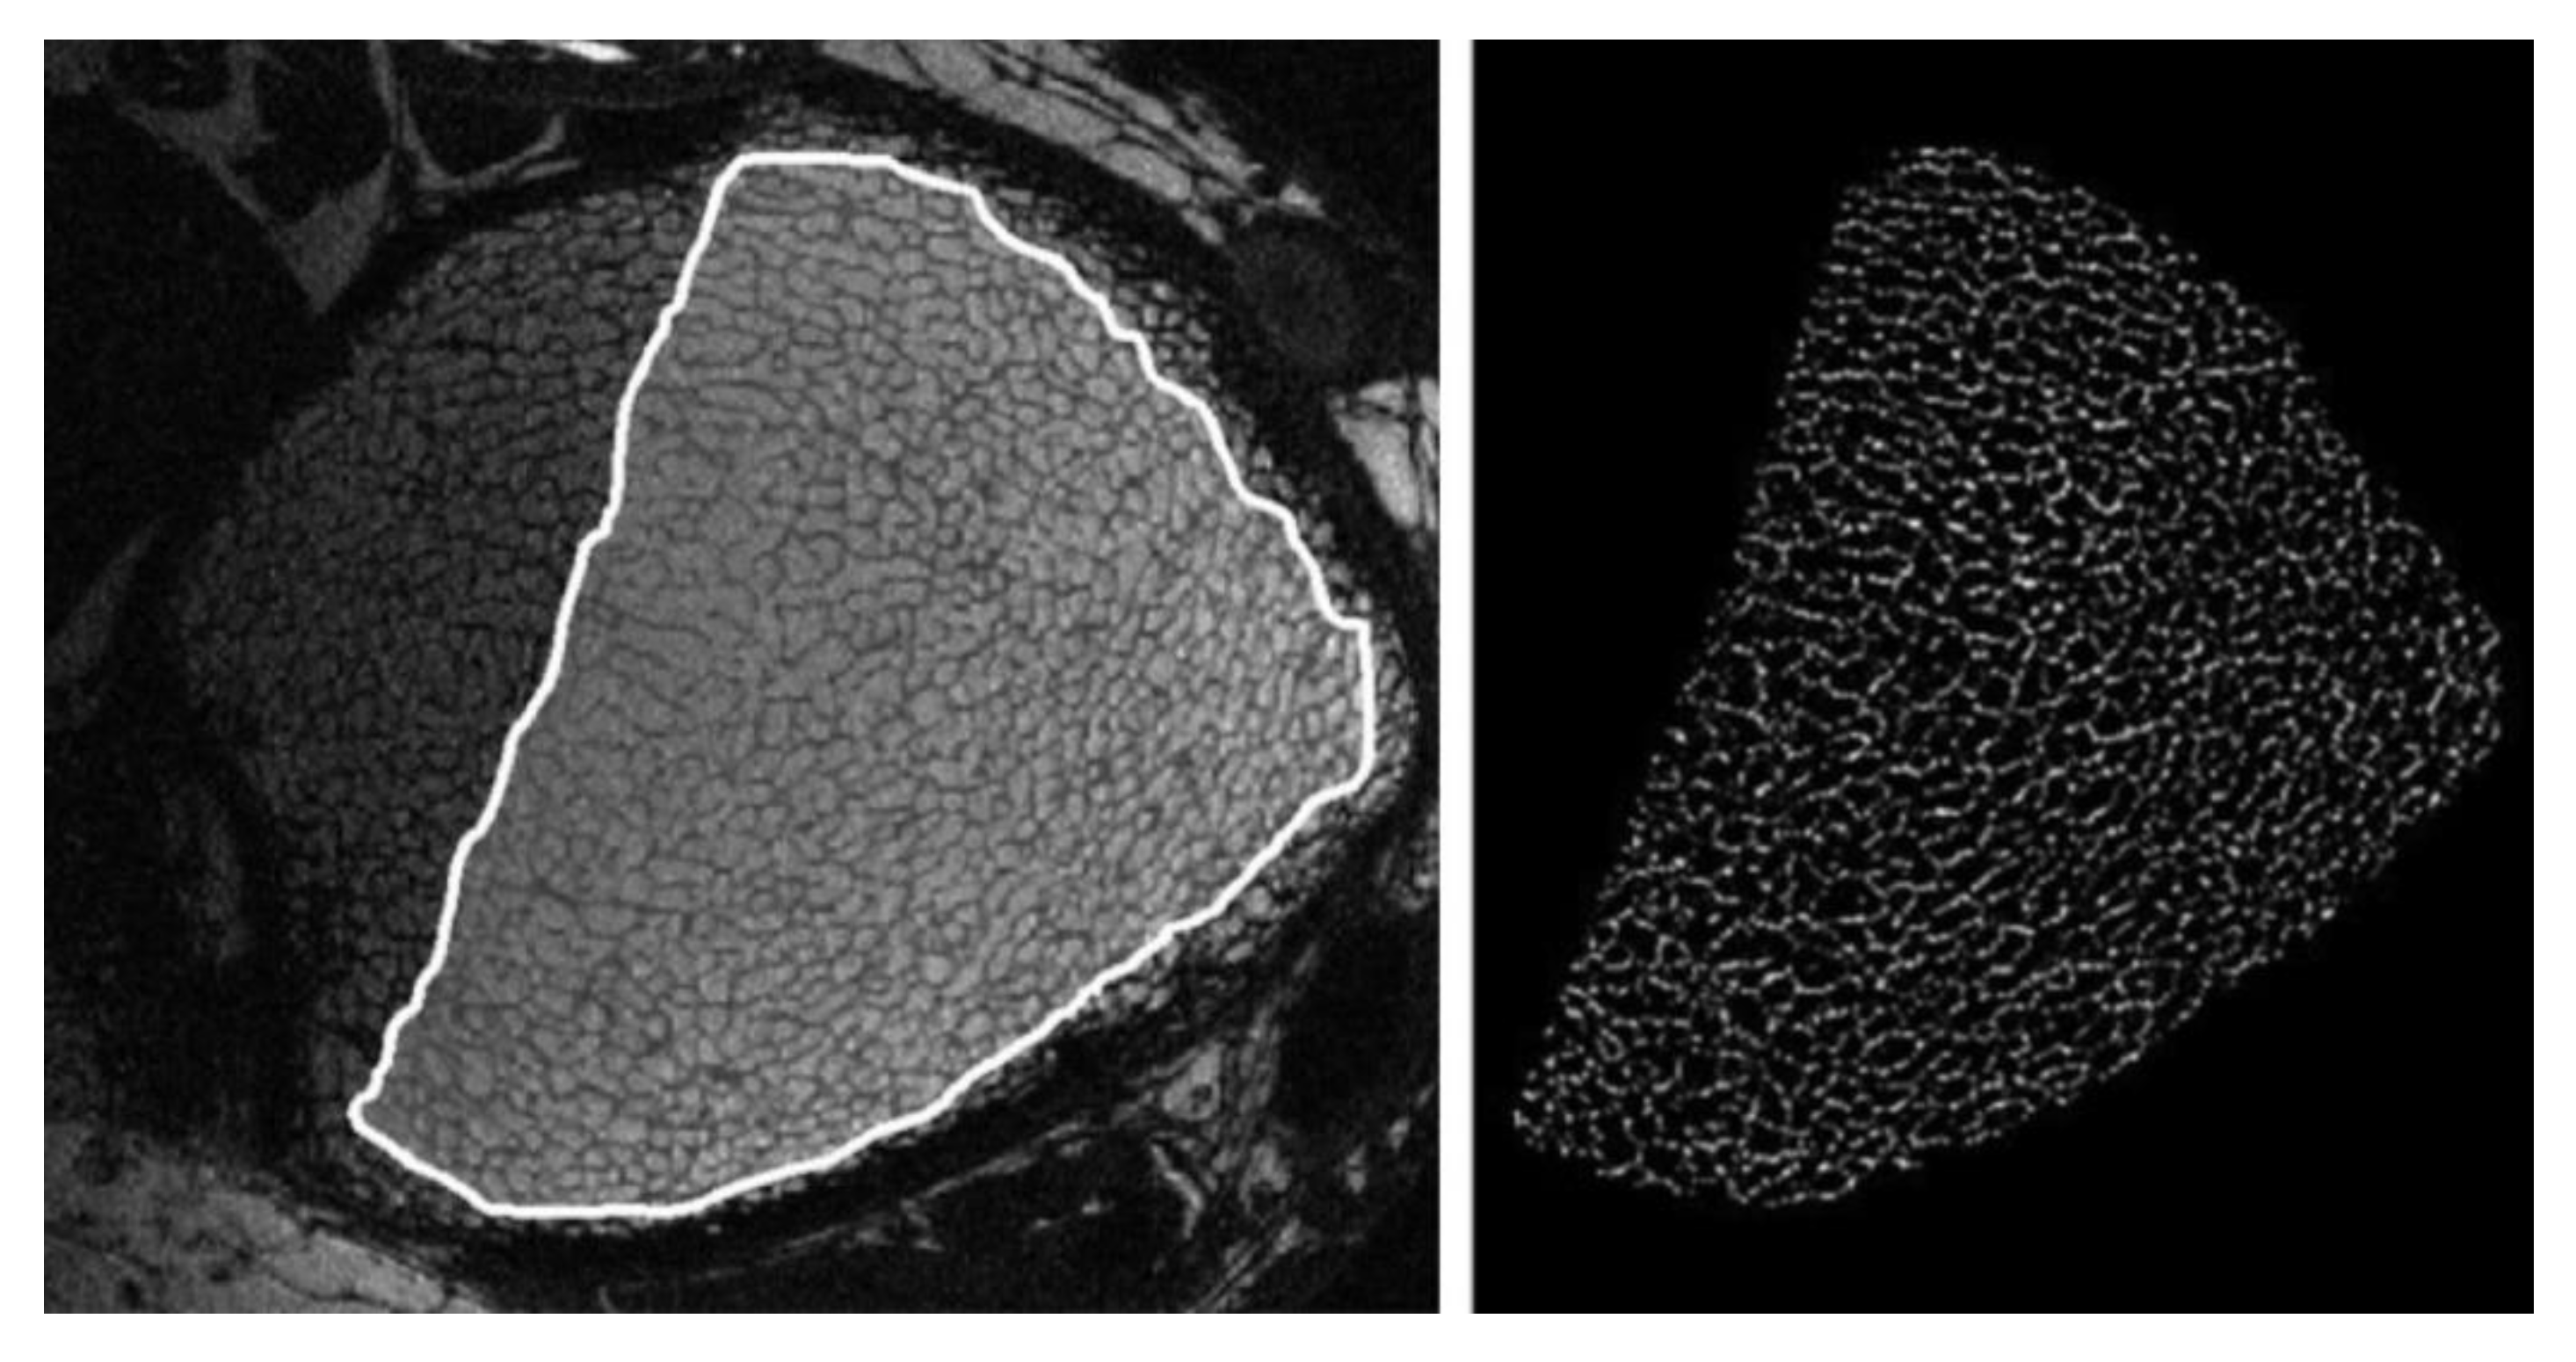

Magnetic resonance imaging (MRI) is a non-ionising technique that provides indirect information on the 3D organisation of bone by measuring the signal coming from the hydrogen atoms contained in the water and the fat compartments of the bone marrow. Thanks to the application of a magnetic field in combination with a radio frequency (RF), the hydrogen atoms can be excited and upon the removal of the RF radiation, the hydrogen atoms relax and emit an RF signal which is detected by RF coils [10]. These RF impulses provide information on the location and the microenvironment of hydrogen atoms [12]. Consequently, information on bone structure can be obtained indirectly by the MRI signal after an image post-processing phase, as visible in Figure 9.

Figure 9.

Processing phases of a magnetic resonance (MR) image of a human distal tibia: selection of the trabecular bone region (left) and its segmentation (right) (reproduced with permission from [54], John Wiley and Sons, 2007).

However, the low amount of water contained in the bone and the presence of the surrounding tissues causes a low signal-to-noise ratio (SNR) in MR images. For this reason, MRI is usually employed at peripheral sites (e.g., distal radius, distal tibia and calcaneus) [10,12]. Furthermore, the SNR is negatively influenced by the voxel size, consequently limiting the analysis resolution to around several hundreds of micrometres [54].